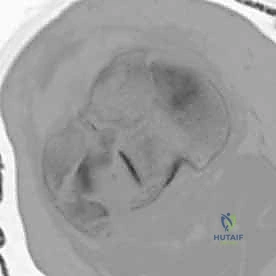

Crucially, the modern orthopedic surgeon must possess a heightened awareness of the posteromedial shear fragment. Historically underappreciated, this specific fracture morphology occurs when the knee is subjected to an axial load while in a flexed and varus position. The medial femoral condyle shears off the posteromedial aspect of the tibial plateau. This is not merely a radiologic curiosity; it represents a highly unstable fracture-dislocation variant. The posteromedial fragment often encompasses the insertion of the posterior cruciate ligament (PCL) and the meniscotibial ligaments. Failure to recognize and independently stabilize this fragment with dedicated posterior or posteromedial buttress plating will inevitably lead to catastrophic posterior subluxation of the femur and rapid varus collapse of the mechanical axis, regardless of the robustness of the lateral fixation.

While the Schatzker system is invaluable, the AO/OTA classification provides a more granular, alphanumeric categorization that is essential for academic research and precise surgical auditing. Bicondylar fractures fall under the 41-C category (complete articular fractures). These are further subdivided into C1 (articular simple, metaphyseal simple), C2 (articular simple, metaphyseal multifragmentary), and C3 (articular multifragmentary). The C3 variant, representing the most complex morphology with extreme articular comminution, tests the limits of surgical reconstruction. Furthermore, modern CT-based classifications, such as the Luo three-column concept, have revolutionized our understanding by dividing the plateau into medial, lateral, and posterior columns. This three-dimensional conceptualization is critical, as it mandates that each fractured column must be independently addressed and stabilized to prevent multi-planar collapse.

The proximal tibia is an asymmetric osseous expansion designed to receive and dissipate the massive loads transmitted across the knee joint. The medial tibial plateau is the primary load-bearing surface. It is anatomically larger, concave in both the sagittal and coronal planes, and supported by bone that is significantly denser and stronger than its lateral counterpart. During the normal gait cycle, the medial plateau sustains approximately 60% to 75% of the total compressive force. This inherent concavity and dense subchondral architecture make it relatively resistant to pure depression fractures; instead, it typically fails in a shear-split pattern.

Conversely, the lateral tibial plateau is smaller, sits slightly higher anatomically, and is distinctly convex in the sagittal plane. The subchondral bone here is notably thinner and more porous. Consequently, the lateral plateau is highly susceptible to depression and impaction injuries when struck by the convex lateral femoral condyle. Understanding these morphological differences is critical during surgical reconstruction. Elevation of the lateral plateau often leaves a massive cavitary void that mandates structural bone grafting to prevent post-operative subsidence, whereas the medial plateau often requires robust anti-glide plating to resist shear forces.